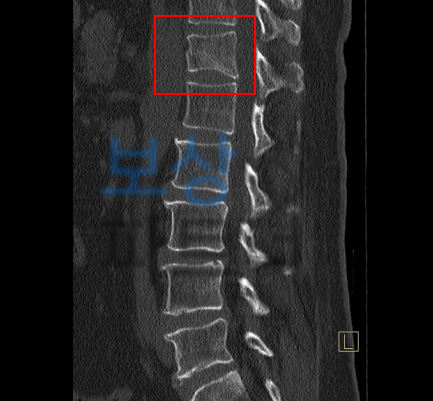

라고 문의해주셨던 김@@님의 실제 보상 사례를 소개해드리겠습니다. 수도권 거주하시는 김@@님께서는 자택에서 발생한 낙상사고로 인해 흉추12번 압박골절 진단을 받으셨습니다.

척추의 골절은 골절 모양의 특성 상 기존 척추의 각도에 영향을 주게 되며

보험 약관에서는 척추 각도의 변형을

장해로 인정하기 때문에 보상받을 수 있는거죠.

보험 약관상 뚜렷한 기형 30%